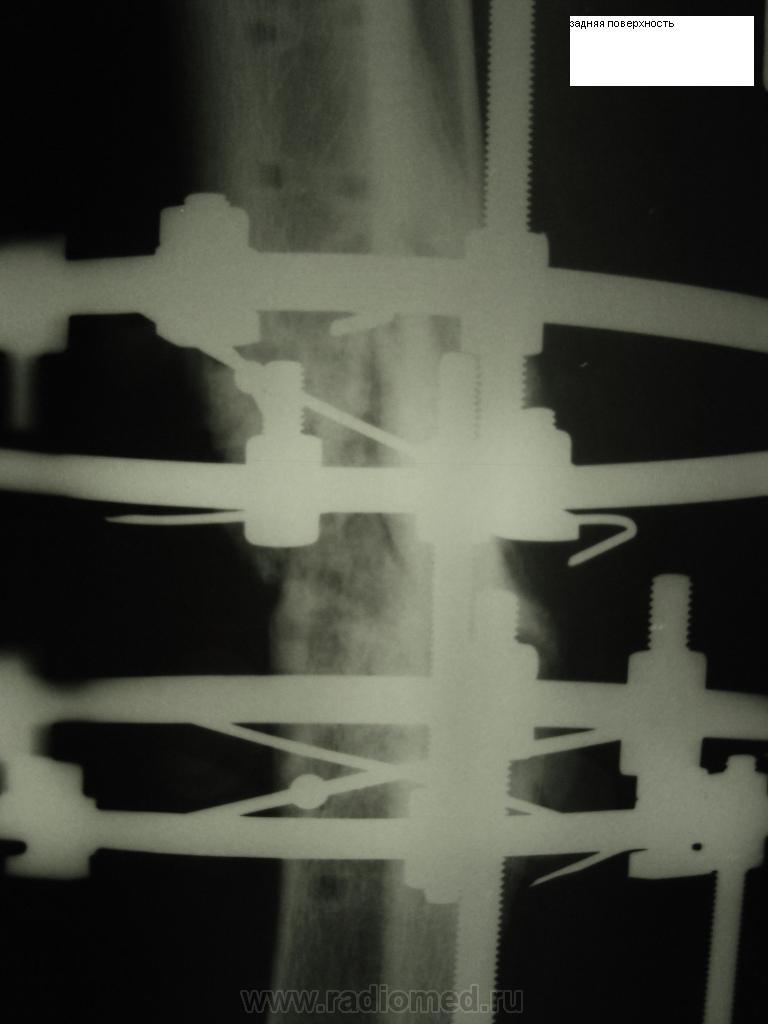

пациент упал на правую ногу в январе, после чего на большую берцовую кость ему сделали МОС пластиной. После снятия пластины подвернул ногу в мае и вот опять перелом "рефрактура". Но мне кажется здесь еще есть диастаз м/у концами отломков с углом открытым кзади????может мне кажется...

На мой взгляд, здесь угол открыт всё же кпереди, но не на 175, а на 174°.

Около 175 градусов, угол открыт кпереди (острием кзади

). Ожидайте формирование ложного сустава.

а я не могу разглядеть угол кпереди